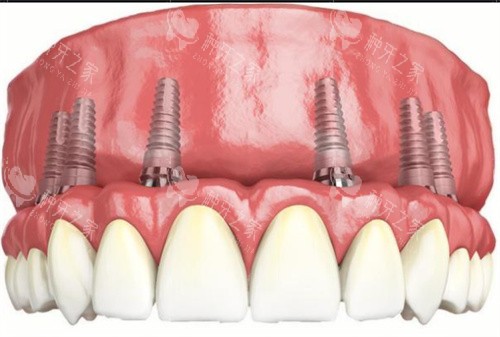

全口种植

全口种植牙解析图

all-on-4全口种植牙模型图